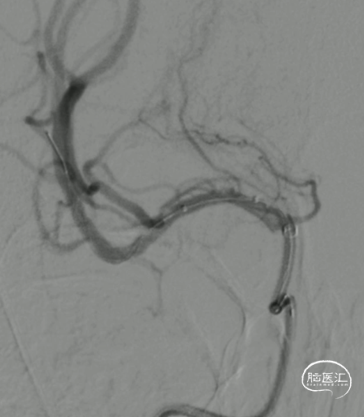

球扩后造影:狭窄明显改善,前向血流明显好转,未见血栓征象,球囊部分回收支架,撤出。

观察15min,未见弹性回缩,正侧位造影。